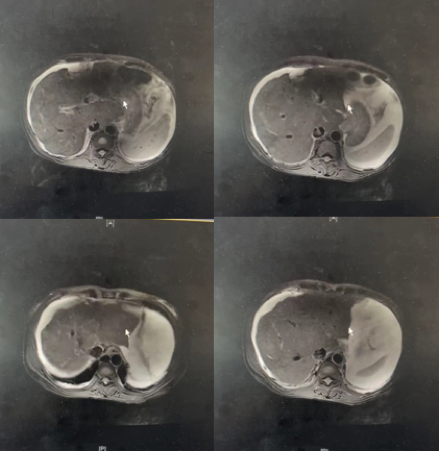

2021年8月复查CT示(图6),肝右叶示直径约3.6cm结节状稍低密度影,中央及周围示斑片、斑点状高密度影,动脉期周围斑片状病灶强化,静脉期及延迟期密度减低。复发转移?

图6.2021年8月复查CT

2021年8月27日我院复查AFP 613.02↑ng/ml,CA125 58.3U/mL,考虑复发。调整用药为“瑞戈非尼 PD-1抑制剂”。